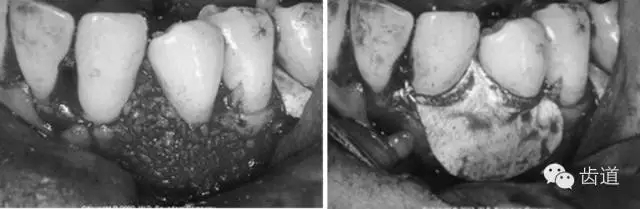

病損區(qū)常規(guī)行牙周翻瓣術(shù),去除感染的牙周袋內(nèi)壁上皮和肉芽組織,根面和骨面清創(chuàng)后,根據(jù)骨缺損和牙根外形選擇并修剪屏障膜,使之能完全覆蓋病損面并固定之,然后齦瓣復(fù)位嚴(yán)密縫合。

6、膜下空間的維持

一般可采取兩種方式來改善單純屏障膜的不足。一種是改進(jìn)型的鈦材加強屏障膜,它是在不可吸收性膜的表面附加鈦絲或鈦網(wǎng),能更好的抵抗牙齦組織的壓力;另一種是支撐和填充材料的聯(lián)合應(yīng)用,即在骨缺損內(nèi)填充不同的植骨材料(包括自體骨、異體脫礦凍干骨、去有機化成分的異種骨、合成的骨替代品等)。

這兩種方法均能有效地防止膜的塌陷和牙齦退縮,保持膜下空間以利再生。在臨床上可根據(jù)病損區(qū)狀況和使用的膜種類來決定其應(yīng)用。但是,目前對加用植骨材料后的臨床療效是否一定優(yōu)于單純應(yīng)用屏障膜仍存在爭議,有待進(jìn)一步的深入比較研究。